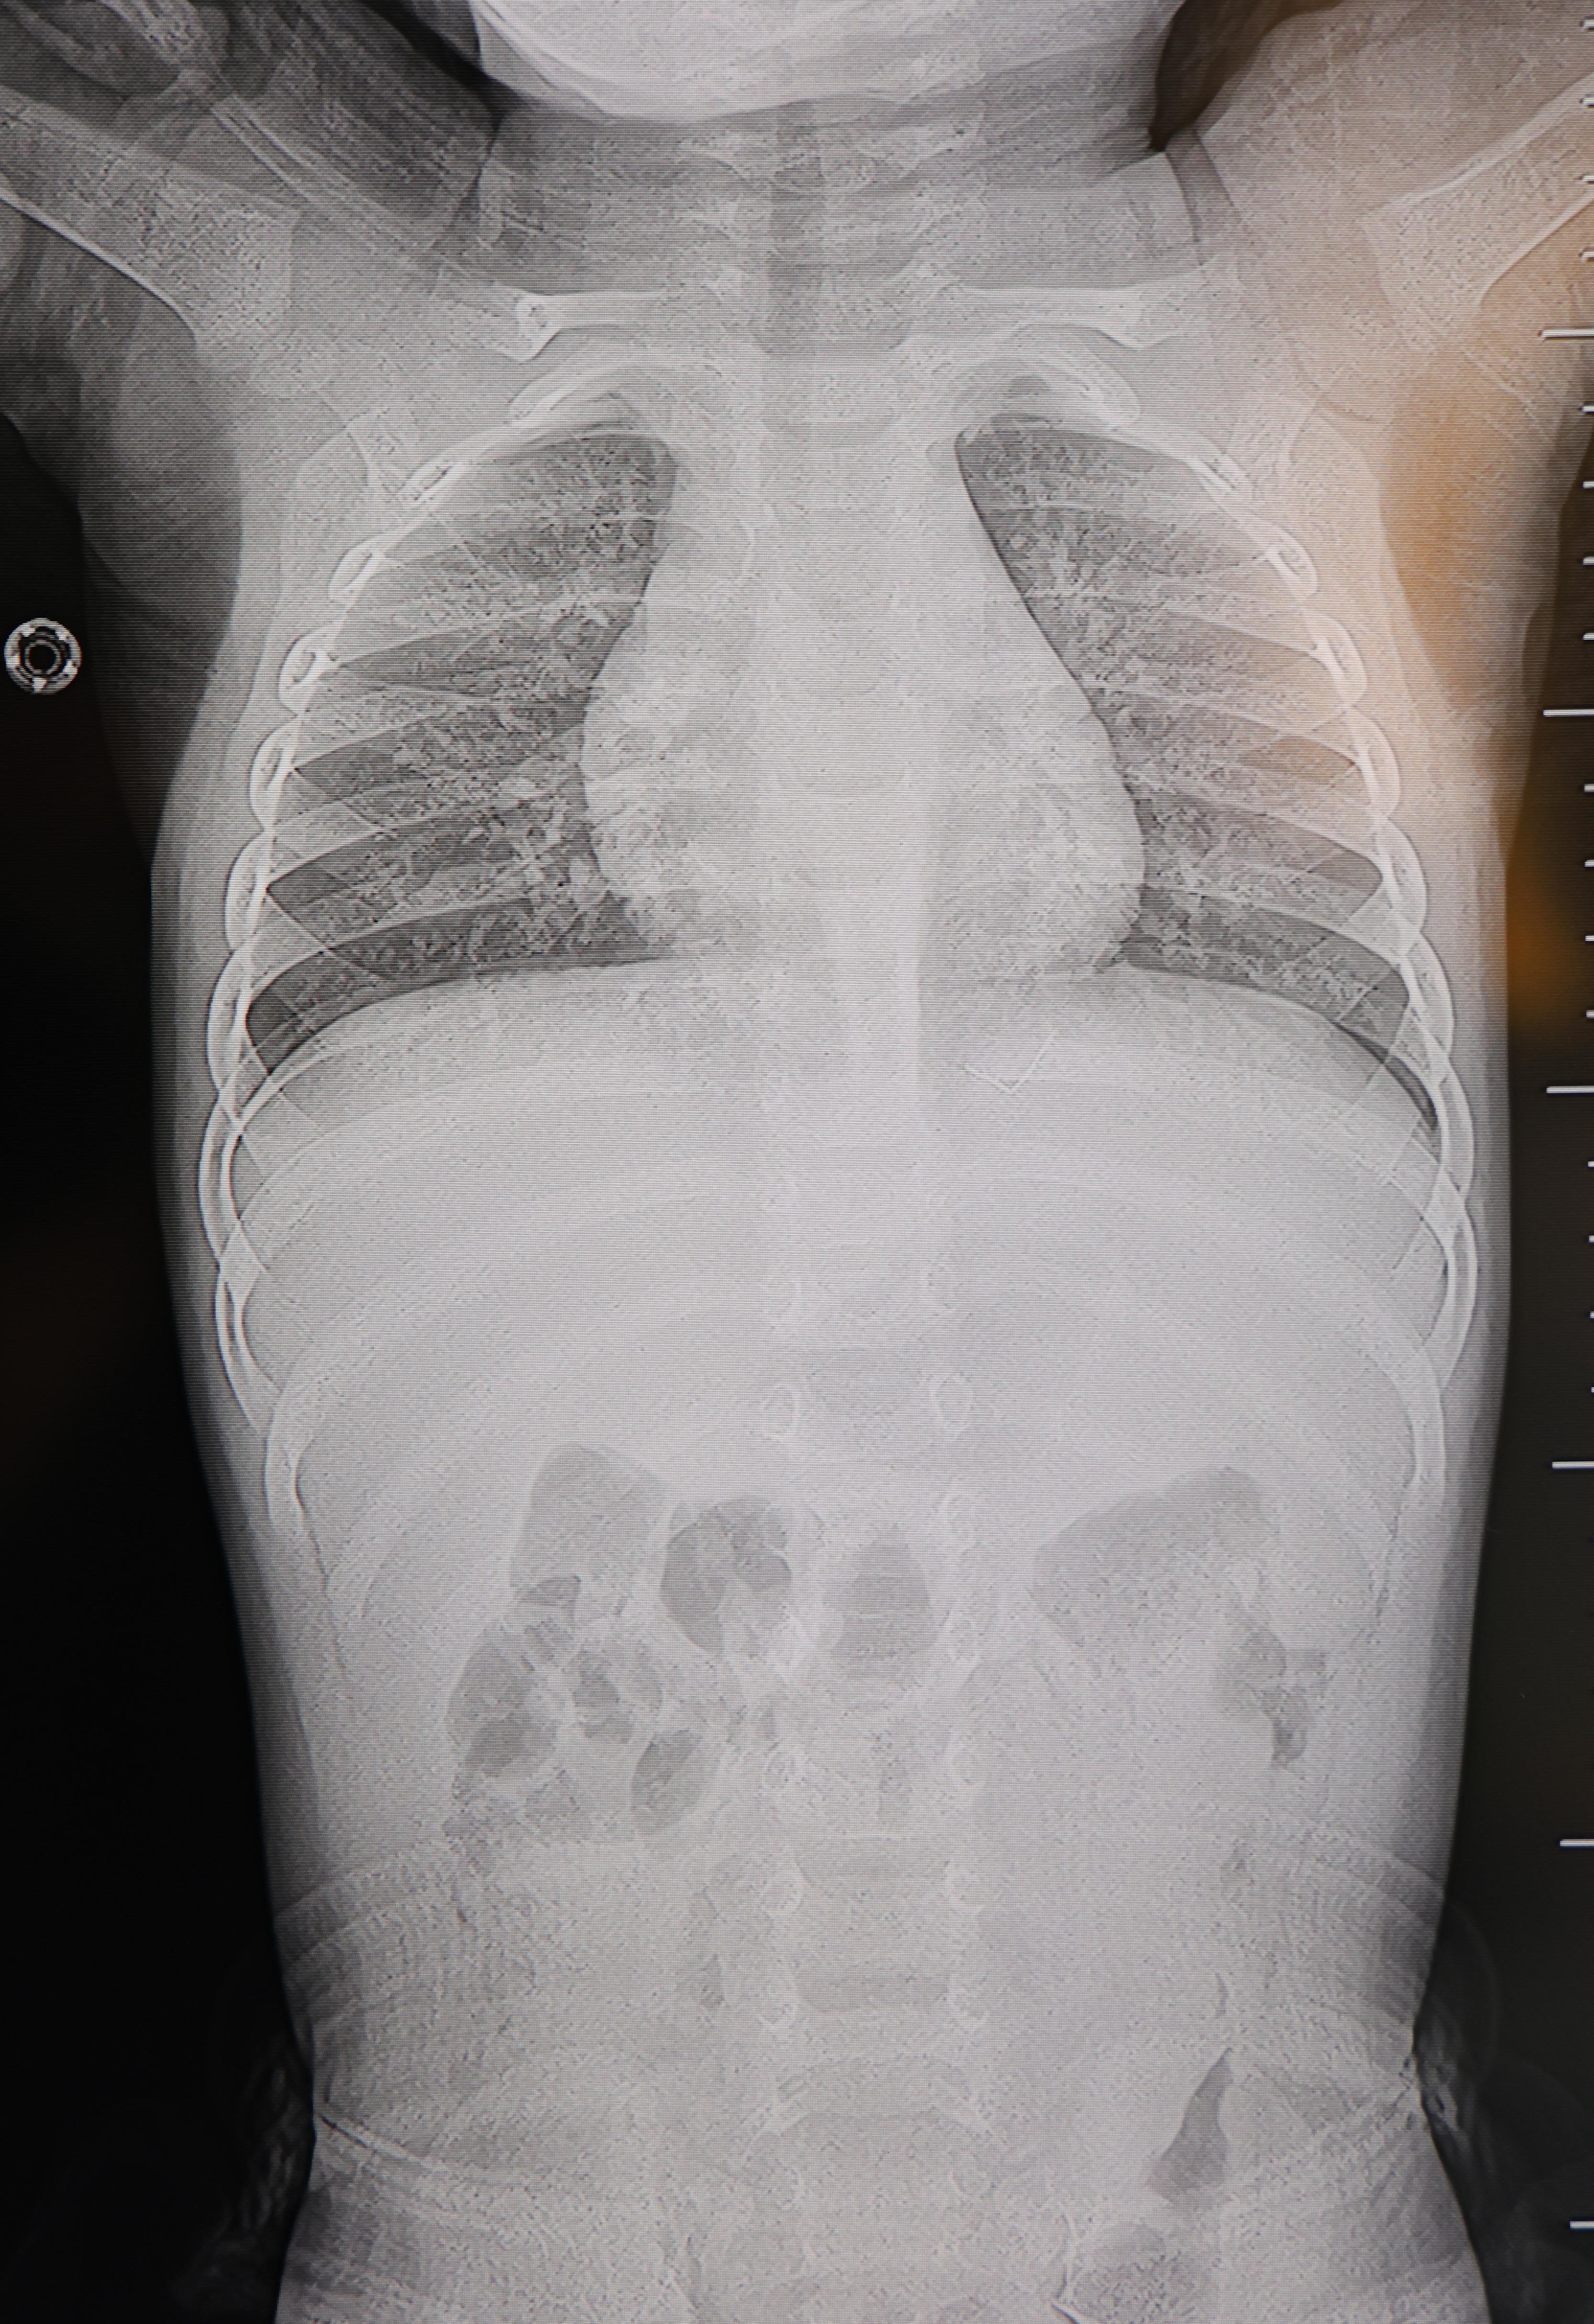

Çocuklarının acı çekmesine dayanamayan aile, son olarak özel bir hastaneye başvurdu. Burada Beyin ve Sinir Cerrahisi Uzmanı Prof. Dr. İdris Altun tarafından yapılan detaylı tetkiklerde korkunç gerçek ortaya çıktı. Bebeğin sırtındaki yabancı cismin cilt altında olduğu, omurilik kanalına çok yakın durduğu ve hareket ederek akciğer zarına doğru ilerlediği tespit edildi.

Durumun ciddiyeti üzerine Prof. Dr. Altun, bebeği genel anesteziyle tamamen uyutmak yerine, lokal anestezi ve sedasyon (sakinleştirme) yöntemiyle ameliyata aldı. Başarılı geçen operasyonla, bölgedeki 2 santimetre uzunluğundaki ince zımba teli benzeri metal cisim çıkarıldı. Bebek aynı gün sağlığına kavuşarak taburcu edildi.

"Sırtında yabancı bir cisim olduğu söylenmiş ancak çıkarılamayacağı ve 8 yaşına kadar beklenmesi gerektiği ifade edilmişti. Bize başvurduğunda yaptığımız tetkiklerde, cilt altında, omurilik kanalına çok yakın ve akciğer zarına doğru ilerleyen bir yabancı cisim tespit ettik. Hastamızı tamamen uyutmadan, lokal anestezi ve sedasyon eşliğinde müdahale ederek lezyonu tamamen çıkardık. Çıkardığımız cismin ince zımba teline benzer, yaklaşık 2 santimetre uzunluğunda metal bir tel olduğunu gördük. Bu yabancı cisim alınmasaydı, bölgede enfeksiyon gelişebilirdi. Enfeksiyon sonucu omurilik kanalında ciddi hasarlar oluşabilir, çocuk büyüdükçe cismin hareket etmesine bağlı olarak omurilikte zedelenmeler meydana gelebilirdi. Ayrıca yana doğru ilerleyerek akciğer zarına ve akciğere batma riski vardı. Bu da enfeksiyona ve ilerleyen süreçte tümörle karışabilecek tablolara neden olabilirdi. Şu an hastamız gayet sağlıklı. Gerekli kontrolleri yaptık ve aynı gün taburcu ettik" dedi.